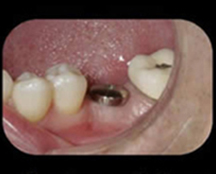

The doctor removes the "healing cap" to place the abutment, then takes an impression of this to send the lab to make your new crown.

The abutment act as a connector between the actual implant and the new crown.